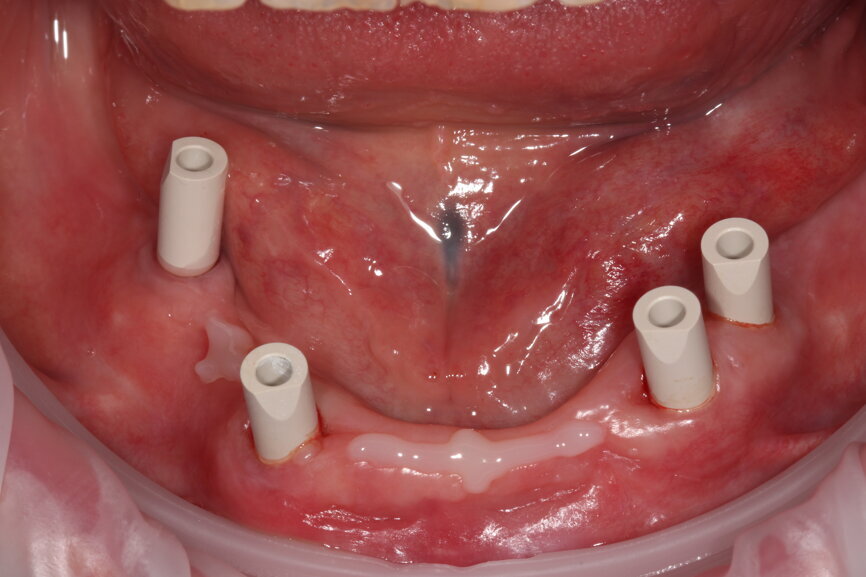

Fig. 10: Scanbodies in situ.

Fig. 14: Scanbodies with composite flow material to increase scan accuracy.

With greater numbers of implants and fewer teeth to act as reference points, intra-oral scanning becomes less reliable—particularly across the arch—so we need to exercise caution and be aware of its limitations. We have used composite flow stuck to the soft tissue to increase reference points for our scanners, increasing their ability to stitch images more accurately together. With this in mind, we cannot assume the scan is accurate and any framework fabricated would be non-passive; therefore, we must use other methods to verify the scan’s accuracy. We have found locking temporary abutments within a composite framework intra-orally the easiest and most reproducible way to do this. It then allows us to design and mill a truly passive framework by Createch and a temporary acrylic bridge.